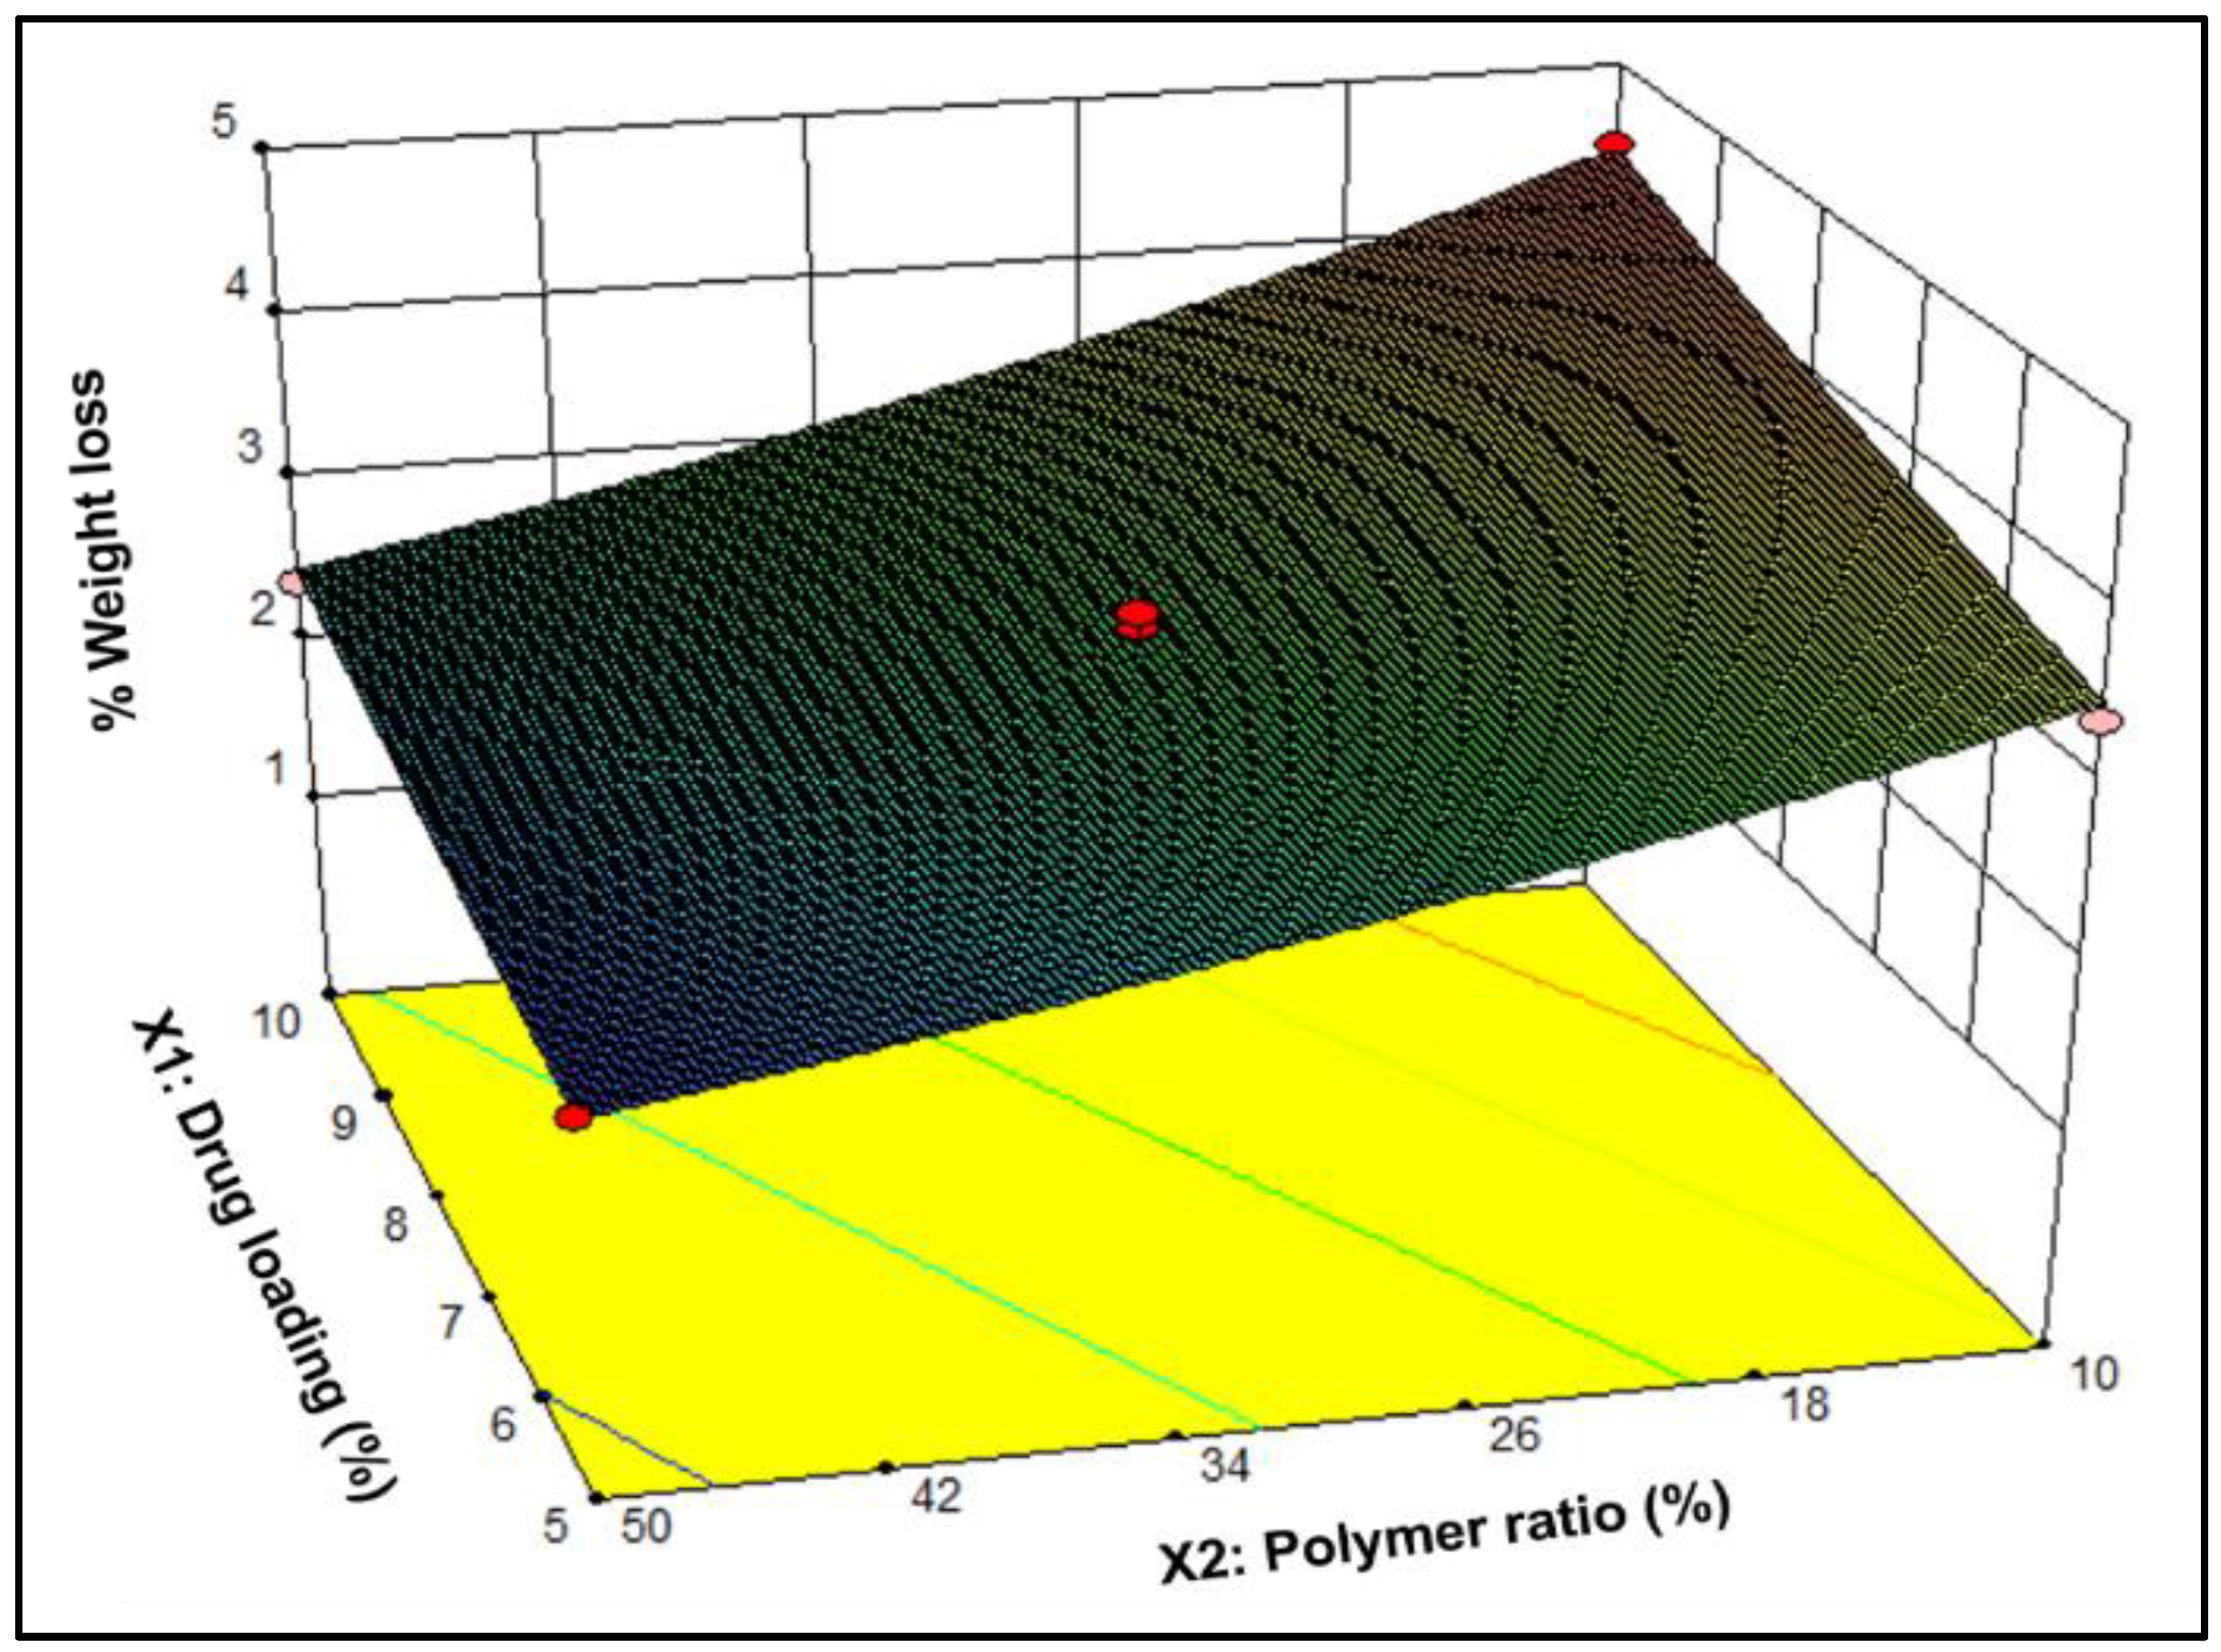

3.1.3. Textural Profiling

| Formulation | 1-Week Drug Release (%) | 2-Week Drug Release (%) | 3-Week Drug Release (%) | 4-Week Drug Release (%) | 8-Week Weight Loss (%) |

|---|---|---|---|---|---|

| N1 | 40.8 ± 3.2 | 62.4 ± 4.6 | 73.2 ± 3.9 | 83.7 ± 1.8 | 3.4 ± 0.3 |

| N2 | 32.4 ± 2.8 | 55.3 ± 4.2 | 69.8 ± 5.2 | 78.0 ± 5.3 | 4.5 ± 0.2 |

| N3 | 23.6 ± 1.0 | 37.8 ± 0.8 | 48.1 ± 0.6 | 58.6 ± 0.7 | 1.9 ± 0.0 |

| N4 | 17.3 ± 0.9 | 26.9 ± 1.2 | 33.1 ± 1.6 | 38.0 ± 1.6 | 2.4 ± 0.0 |

| N5 | 29.8 ± 1.6 | 46.8 ± 1.9 | 59.0 ± 1.9 | 67.0 ± 1.8 | 2.9 ± 0.1 |

| N6 | 29.6 ± 2.3 | 44.7 ± 2.3 | 55.0 ± 2.5 | 62.5 ± 2.4 | 3.0 ± 0.1 |

| N7 | 29.3 ± 2.4 | 44.5 ± 2.0 | 56.9 ± 2.4 | 66.0 ± 2.2 | 3.1 ± 0.0 |